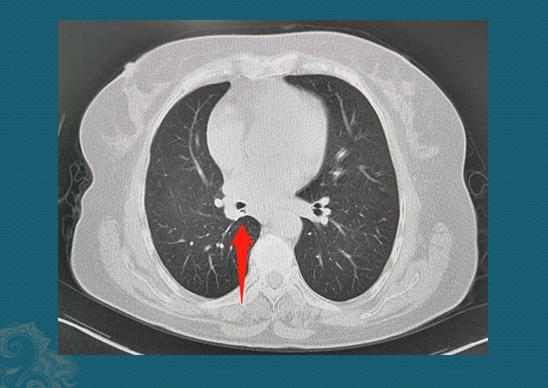

这位老爷子比较幸福,儿子给买了一辆代步三轮车,没事开着出去兜兜风,拐弯时没控制好方向,翻沟里了,肋骨受到挤压,做了CT:

肋骨没有骨折,但左肺长肿瘤了,大约1.8cm的混合磨玻璃结节,伴有胸膜牵拉。精准一点来说,有两个重要特点:

1.结节边缘清晰,是比较淡的磨玻璃影,偏外侧有不规则的白色实性成分,属于混合磨玻璃结节;

2.结节外侧伴有胸膜牵拉。

以上两条就符合一个定律:边界清晰的混合磨玻璃结节伴有胸膜牵拉,诊断肺癌极少错误(多为肺腺癌),甚至不需要穿刺取病理。老爷子半年前做了胸腔镜手术,病理是浸润性肺腺癌,未侵犯壁层胸膜。这种情况五年生存率极高!